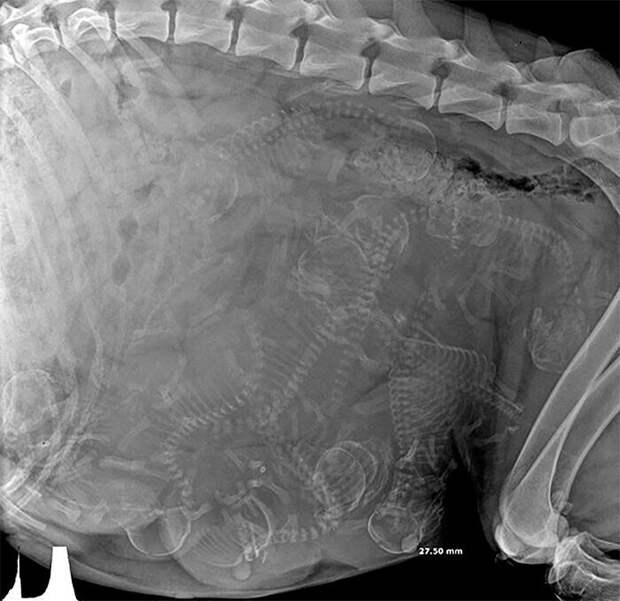

Рентгеновский снимок беременной собаки